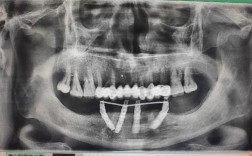

种植牙能否戴牙冠,首要前提是种植体与牙槽骨完成“骨结合”,骨结合是指种植体表面与周围骨组织之间形成直接的 structural connection,两者紧密结合,如同天然牙根与牙槽骨的关系,这一过程是种植牙稳定性和长期使用的基础,若骨结合未充分形成就过早戴牙冠,可能导致种植体松动、脱落甚至失败。

骨结合的时间受多种因素影响,通常需要3-6个月,但部分患者可能需要更长时间,骨结合的速度与牙槽骨的质量、患者的身体状况、种植体的设计等密切相关,牙槽骨条件好、骨质致密的患者,骨结合可能更快;而牙槽骨萎缩、需要进行植骨手术的患者,则需要额外等待植骨区域愈合,骨结合时间会相应延长。

- 定期复查:按医生要求复查(通常术后1周、1个月、3个月),通过X线片检查骨结合情况,及时调整治疗方案。